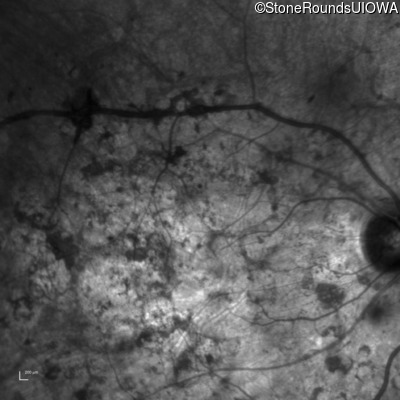

Infrared Fundus Photograph - Right - Hand Motion

Exemplar